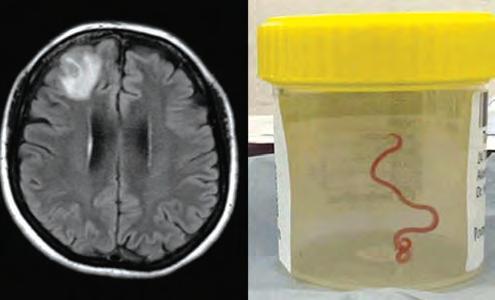

Australia.- “Definitivamente no era lo que esperábamos. Todo el mundo quedó en shock”, dijo la doctora Hari Priya Bandi, la neurocirujana que operó a la paciente. La mujer, de 64 años, sufría lo que los médicos llamaron una “constelación inusual de síntomas”: dolor de estómago, tos y sudores nocturnos, que evolucionaron hacia crecientes problemas de memoria y depresión. La mujer ingresó en el hospital y, posteriormente, una exploración reveló “una lesión atípica en el lóbulo frontal derecho del cerebro”. Pero la causa de su trastorno solo fue revelada con el bisturí de la doctora Bandi durante una biopsia. Los médicos dijeron que el parásito rojo pudo haber estado vivo en el cerebro de la mujer hasta por dos meses. La mujer, que vivía cerca de una zona de un lago en el estado de Nueva Gales del Sur, se está recuperando bien. Se cree que éste es el primer caso que se documenta sobre invasión y desarrollo de larvas en el cerebro humano, informaron los investigadores en un estudio en la revista Emerging Infectious Diseases (Enfermedades Infecciosas Emergentes). La neurocirujana que encontró el gusano describió cómo apenas había comenzado a tocar una parte del cerebro que había aparecido extraña durante las exploraciones, cuando sintió al gusano. “Pensé, Dios mío, se siente muy raro, esto es totalmente anormal”, contó la doctora Bandi.

“Y entonces pude sentir realmente algo, tomé mis pinzas, lo extraje y pensé: ‘¡Dios! ¿Qué es eso? ¡Se está moviendo!”. “Todo el mundo estaba en shock. Y el gusano que encontramos se movía alegremente, con bastante vigor,

En un caso nunca antes documentado en el mundo, científicos informaron que encontraron un gusano vivo de 8 cm en el cerebro de una mujer en Australia. La “estructura en forma de cuerda” fue extraída del lóbulo frontal lesionado de la paciente durante una cirugía en Canberra.

fuera del cerebro”, dijo. Después consultó a su colega Sanjaya Senanayake, especialista en enfermedades infecciosas, sobre lo que deberían hacer. “Todos en ese quirófano sufrieron el shock de su vida cuando [la cirujana] tomó unas pinzas para detectar una anormalidad y la anormalidad resultó ser un gusano vivo, de color rojo claro, de 8 cm, que se retorcía”, dijo la doctora Sanjaya Senanayake, especialista en enfermedades infecciosas del Hospital de Canberra.

“Incluso si se elimina el factor de asco, esta es una nueva infección nunca antes documentada en un ser humano”.

Los investigadores advierten que el caso pone de relieve el creciente peligro de que las enfermedades e infecciones se transmitan de los animales a las personas. El nematodo o gusano redondo

Ophidascaris robertsi es común en las pitones de alfombra, serpientes no venenosas que se encuentran en gran parte de Australia. Los científicos dicen que lo más probable es que la mujer contrajera el parásito después de recolectar un tipo de maleza nativa, verdes de Warrigal, junto a un lago cerca de donde vivía. En un artículo en la revista Emerging Infectious Diseases (Enfermedades Infecciosas Emergentes), Mehrab Hossain, experto australiano en parasitología, dijo que sospecha que la mujer se convirtió en una “huésped accidental” después de usar las plantas recolectadas, contaminadas por heces de pitón y huevos de parásitos, para cocinar. “Anteriormente no se había informado de la invasión del cerebro por larvas de Ophidascaris”, escribe el doctor Hossain.